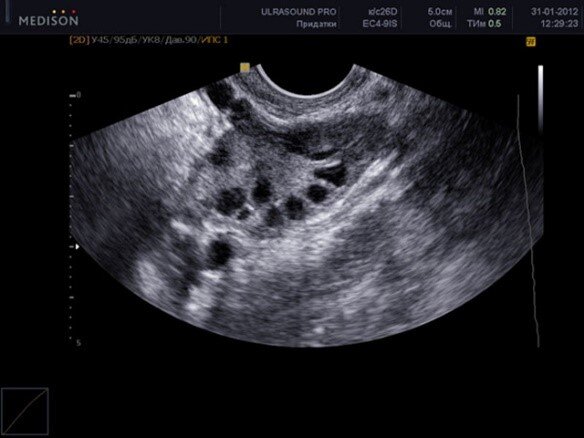

В норме яичник выглядит вот так. Он напичкан фолликулами - это пузырьки или мешочки с жидкостью, где развиваются яйцеклетки, что бы затем встретиться со сперматозоидом.

*здоровый яичник

И это лишь те, которые мы видим, об остальных мы только знаем, так как 120 дней развивается каждый из этих фолликулов, из 120 дней, только последние 14 дней они видны на УЗИ, а остальные растут и ждут своего часа. 10-15 пузырьков начинают расти каждый цикл и лишь один вырывается в лидеры, чтобы увидеть «просвет» маточной трубы (и либо дать жизнь, либо уйти в небытие, также как и его коллеги по яичнику).